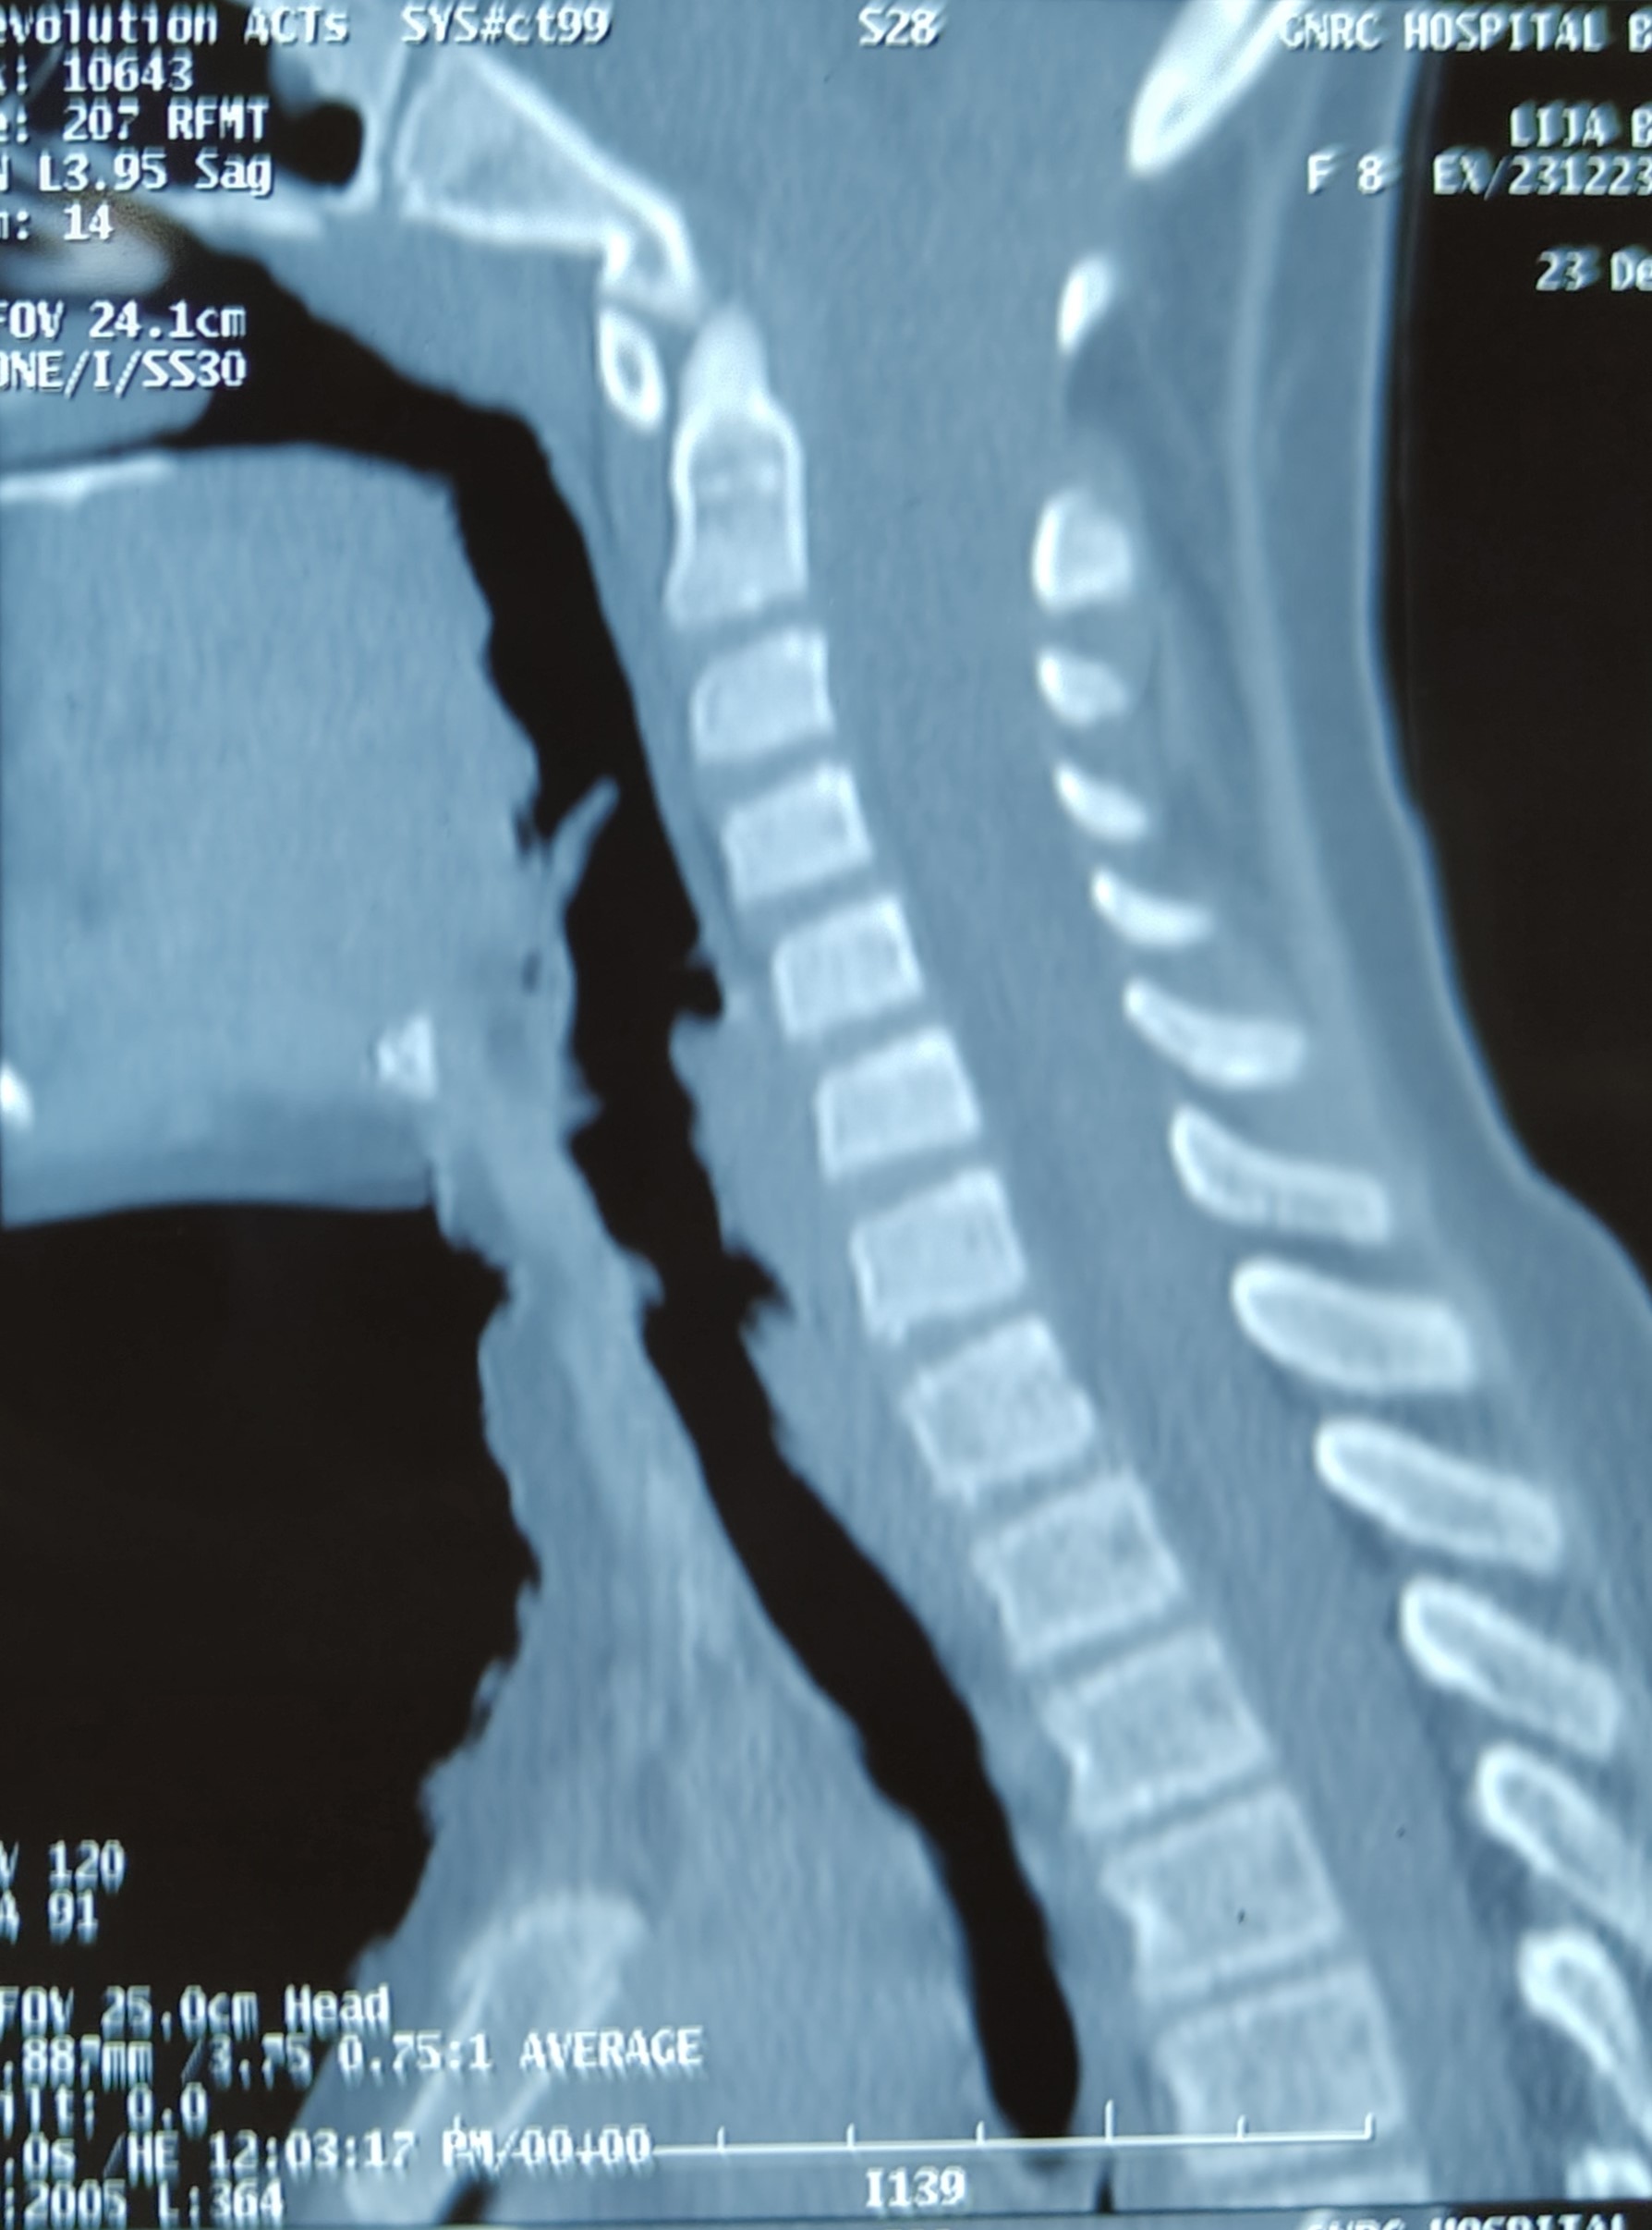

An 8 yr old child presents with squint and headache . CT , MRI shows Chiari 1 malformation with cord signal change

• Is there any instability ?

• Is there any impacted tonsil?

• What will be better..only bony decompression, duroplasty, tonsillar resection?